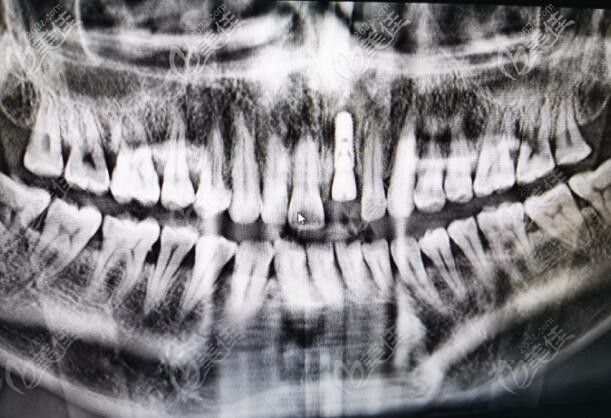

李煥初,畢業(yè)于佛山口腔,廣州學(xué)士,進(jìn)修于,從事口腔醫(yī)療近十年,在種植修復(fù)領(lǐng)域有頗深的造詣。